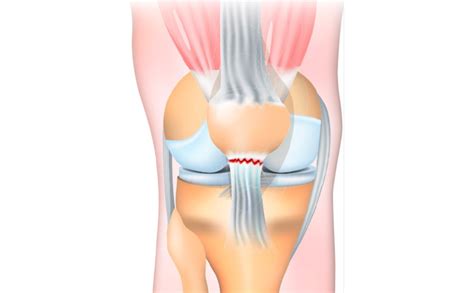

The patellar tendon, also known as the patellar ligament, is a thick band of tissue that connects the patella to the tibia. It plays a vital role in the extension of the knee joint, allowing for movements such as walking, running, and jumping. The tendon is under constant stress and strain, making it susceptible to injuries, particularly in athletes and individuals involved in high-impact activities.

• Acute Trauma: A sudden, forceful contraction of the quadriceps muscle can cause the tendon to tear. This often happens during activities like jumping, landing, or sudden changes in direction.